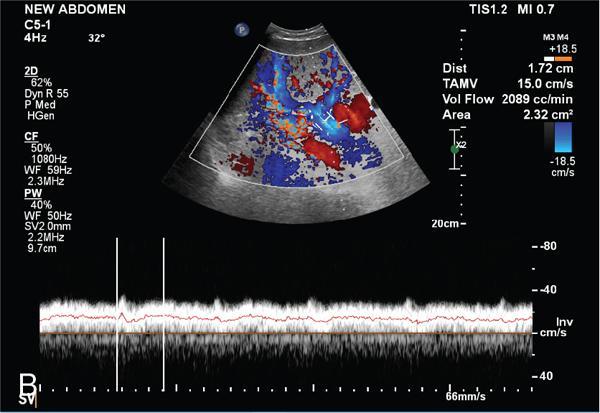

Shrinivas B. Desai, Ritu K. Kashikar, Aman Snehil, Ajay Jhaveri Cirrhosis is a late stage of irreversible scarring of the liver causing abnormality in liver structure and function. Multiple conditions and factors can cause repeated liver damage and scarring ultimately leading to cirrhosis. The most feared complication of liver cirrhosis is the development of hepatocellular carcinoma (HCC). Portal hypertension (PHT) is seen with a variety of conditions but cirrhosis happens to the most important cause. Imaging plays a vital role in noninvasive diagnosis and treatment planning of both cirrhosis and PHT. Liver imaging reporting and data system (LI-RADS) is a standardized reporting system assigning an observation risk of representing HCC. This chapter focuses on discussing aetiologies and imaging of PHT with a lucid review of L1-RADS 2018 version. The portal blood circulation is a unique circulatory circuit as it connects two capillary beds between the liver parenchyma at one end and the gastrointestinal tract and splenic parenchyma at the other end. The portal system ramifies in the liver and ultimately ends in the hepatic sinusoids from where the blood ultimately drains into the inferior vena cava (IVC). The portal vein (PV) originates from the capillary beds in the stomach, intestine and the spleen. The main PV is formed behind the neck of the pancreas by the confluence of the superior mesenteric vein (SMV) and splenic vein. It continues to the porta hepatis where it bifurcates into the left and right branches as it carries nutrient rich but oxygen poor blood to the liver (Fig. 9.9.1). The PV makes up for 75%–80% of the liver’s blood supply while the hepatic artery which arises from the celiac trunk makes up for the remaining 25%. A pathological increase in the portal venous pressure is referred to as PHT. PHT is most often a sequel of chronic parenchymal liver disease and leads to major life-threatening complications due to bleeding from the collateral circulation (most commonly oesophageal varices). Direct measurement of portal pressure (PP) is invasive and often not feasible in most patients and thus imaging plays an important role in the diagnosis of PHT and its complications. The normal portal venous pressure ranges between 5 and 10 mmHg, which is the equivalent of 7–14 cm H2O. The normal hepatic venous pressure gradient (HVPG) is the pressure gradient between the PV and the IVC, is typically 1–5 mmHg. Presence of PHT is indicated by a wedged hepatic venous pressure of more than 5 mmHg. Other definitions include a splenic pressure of more than 15 mmHg or an intraoperative PP of greater than 30 cm H2O. The complications of PHT are seen when HVPG is greater than 10 mmHg and hence this value defines clinically significant PHT. Variceal bleeding is seen with a pressure greater than 12 mmHg. In ideal conditions, the portal circuit is a high flow, low resistance circuit as it has to allow substantial flow rates of 700–1000 mL/min to the hepatic parenchyma from the gastrointestinal tract. Anatomical changes in the organization of the hepatic lobule can result in rise in the portal resistance. These can occur in the form of collagen deposition in the space of Disse, fibrotic scars formed due to regenerative nodule (RN) formation, loss of normal elasticity of the endothelium and distal venous thrombosis. Changes in splanchnic haemodynamics due to factors that increase splanchnic blood flow and increase in intrahepatic vascular resistance due to transformation of stellate cells into myofibroblasts also contribute to the increase in PP gradient. In Western countries, alcoholic cirrhosis and viral cirrhosis are the leading causes of PHT and oesophageal varices. The viral causes form majority of cases leading to cirrhosis and PHT in the Far East and Middle Eastern countries while Schistosomiasis remains an important cause in the African countries. Worldwide, nonalcoholic steatohepatitis (NASH) and hepatitis C are the emerging causes of chronic liver disease (CLD) and PHT. PHT can be classified as cirrhotic and noncirrhotic depending on whether it is associated with cirrhosis or not. This distinction is important as noncirrhotic causes like PV thrombosis are at high risk of development of bleeding but tend to have a better chance of surviving a variceal bleed than a patient with decompensated alcoholic cirrhosis due to preserved hepatic synthetic functions in the former. PHT can also be classified on the basis of the location of the pathology into prehepatic, hepatic and posthepatic causes. Hepatic causes can further be divided into presinusoidal, sinusoidal and postsinusoidal. The causes of portal hypertension have been denoted in Table 9.9.1. The direct measurement of the PP by measuring the HVPG is invasive, expensive not readily available in all patients. Thus, imaging plays an important role in the diagnosis of PHT. Various modalities are used for the imaging diagnosis of PHT. Ultrasonography (USG) and Doppler evaluation have the advantage of being inexpensive, readily available and bedside modality (Table 9.9.2). The role of ultrasound and Doppler in imaging of PHT is to: Grey scale imaging is useful in evaluating the splenoportal anatomy. The evaluation should begin with the liver morphology. Signs of cirrhosis like nodularity of the liver surface with relative atrophy of the right lobe and prominence of the left lobe and caudate should be looked for. Hepatic echotexture appears coarse and more echogenic (Table 9.9.3). Increase in portal venous diameter is a sign of PHT (Fig. 9.9.2). Portal venous diameter of more than 13 or 15 mm has low sensitivity for diagnosing PHT of only 40%–12.5%, respectively. Absolute measurement of the portal diameter as a sign of PHT is also fallacious as in presence of collateral circulation or hepatofugal flow; there may actually be a decrease in the PV diameter. Therefore, a more accurate sign is respiratory variation of PV diameter. An increase in PV diameter of less than 20% with deep inspiration has been reported to indicate PHT with a sensitivity of 80% and specificity of 100%. This has been reported to be an accurate indicator of cirrhosis. Hepatic vein straightness, uniformity of vein wall echogenicity and visualization of at least 1 cm segment of the hepatic vein are the parameters used for evaluation. Splenomegaly is defined as bipolar splenic diameter of greater than 12 cm or largest splenic cross-sectional area passing through the hilum of greater than 45 cm2, and occurs secondary to PHT (Fig. 9.9.3). A total of 65%–80% patients with cirrhosis have splenomegaly on ultrasound. Patients with cirrhosis due to viral hepatitis and primary biliary cirrhosis show splenomegaly more frequently than those with alcoholic cirrhosis. This is an accurate sign of PHT. USG is extremely sensitive with respect to detecting subclinical ascites. Perihepatic space is the most usual site of visualization of minimal ascites. In normal subjects, this ratio is approximately 0.07 and a value above 0.1 suggests the diagnosis of PHT with a 95% sensitivity and specificity. The normal spectral waveform of the hepatic artery is a low resistance flow pattern with forward flow in diastole and a resistivity index in the range of 0.5–0.7. In PHT, the resistivity index of the hepatic artery increases with high resistance flow pattern due to increased peripheral vascular resistance. Resistance index (RI) > 0.78 in the intrahepatic branches of the hepatic artery has been reported to have a sensitivity of 50% and a specificity of 100% for the detection of PHT (Fig. 9.9.11). Pulsatility index (PI) > 1.05 suggests severe PHT with a sensitivity of 86% and specificity of 88% (Fig. 9.9.11). Patency of hepatic veins should be evaluated to rule out Budd–Chiari syndrome as a cause of PHT. The normal hepatic venous waveform (HVW) reflects right atrial activity and this results in a triphasic waveform with one positive and two negative waves. In PHT, this waveform becomes monophasic or biphasic. A monophasic HVW has a sensitivity and specificity of 74% and 95%, respectively, in the diagnosis of severe PHT (Fig. 9.9.12). Dilatation of the splanchnic veins – the SMV and the splenic vein – more than 11 mm are suggestive of PHT with a sensitivity and specificity of 72% and 100%, respectively. A reduction in the respiratory variation of the splenic vein and SMV to less than 40% had a sensitivity and specificity of 79.7% and 100%, respectively, for the diagnosis of PHT (Fig. 9.9.13). The splenic artery reveals an increase in the resistivity index and an RI of >0.63 and a PI of >1 have a sensitivity and specificity of 84.6% and 70.4% for the diagnosis of PHT. Presence of portosystemic collaterals like patent paraumbilical vein, dilated left gastric and short gastric veins are 100% specific sign for PHT (Figs. 9.9.14–9.9.16). Recanalization of the paraumbilical vein, known as the Cruveilhier–Baumgarten syndrome is observed in 43% of patients with PHT, and this is the easiest collateral to assess during the US examination. Various portosystemic collaterals that occur in PHT have been discussed in details in subsection on CT findings in PHT. No Doppler parameter is considered reliable enough to measure PP with sufficient accuracy for use in clinical practice. Oesophageal varices are often present in patients with portosystemic collaterals. Appearance or increase in number of collaterals along with splenomegaly has a high association with variceal formation and growth. USG helps in diagnosis of prehepatic causes like portal stenosis or thrombosis by demonstrating the patency and morphology of the splenoportal system. Arteriovenous fistulae and tumours causing vascular thrombosis as aetiology can be readily detected. USG helps in diagnosis of features of cirrhosis and thus helps differentiate noncirrhotic causes of PHT. USG allows diagnosis of fatty liver disease, which is an emerging cause of cirrhosis. Among the posthepatic causes, USG aids in establishing the diagnosis of Budd–Chiari syndrome by demonstrating the patency and morphology of the IVC and hepatic veins. Owing to the inability of CT to detect flow direction, portal flow rates or pressure gradients, CT is not the primary modality in diagnosis of PHT. Similar to USG dilatation of portosystemic system is a feature of PHT (Fig. 9.9.17). Changes in cirrhosis if present can be seen in the form of surface nodularity, nodules and fibrous septae. CT plays an important role in diagnosis of portal venous thrombosis and evaluating its extent. An acute thrombus is seen as a hypodense filling defect in the vessel causing distension of the venous lumen. Surrounding fat stranding can be seen. A chronic thrombus appears as an eccentric filling defect usually along the wall and is often associated with decrease in vessel diameter. Calcification may be seen in chronic thrombi. Multidetector computed tomography (MDCT) is a useful tool to evaluate portosystemic collateral circulation and recognize complications of PHT. 3D angiography can help understand portal venous and complex variceal anatomy and plan treatment. The various portosystemic collaterals are discussed below. They can be classified into those draining into superior vena cava (SVC) and those draining into the IVC. Magnetic resonance imaging (MRI) is a noninvasive modality used in the evaluation of PHT without the use of ionising radiation. It provides evaluation of parenchymal abnormalities, collaterals and characterization of tumours (Fig. 9.9.28). Spin echo sequences allow characterization of liver masses and liver parenchyma. Loss of flow void allows for detection of thrombosis. Time-of-flight (TOF) angiography is useful in assessing the portal venous system and allows for successful detection of PV thrombosis. The disadvantages of TOF are motion artefacts caused by breathing, long acquisition times and incomplete coverage of the portal venous system. Novel imaging techniques include phase contrast, T1 mapping and magnetic resonance elastography (MRE). The advantage of phase contrast over TOF imaging is that phase contrast imaging acquires information regarding the flow direction in addition to the information regarding the flow velocity. On-phase contrast images signal within vessel is hyperintense when flow is cranial and hypointense when flow is caudal. Look-Locker imaging technique using gradient echo (GRE) MRI sequences with inversion recovery pulse is used to quantify fibrosis by measuring precontrast T1 relaxation times. Interventions in PHT can be aimed at diagnosis or more commonly at management of complications of PHT. HVPG measurement, which is the gold standard for the diagnosis of PHT, can be achieved through cannulation of the PV. Transjugular hepatic biopsy is another diagnostic invasive technique that also allows indirect measurement of PP. Disadvantages include deterioration of hepatic function caused by diversion of portal venous blood flow and shunt dysfunction. TIPSS is contraindicated in patients with congestive heart failure, severe pulmonary hypertension, severe tricuspid regurgitation and hepatic failure. In this technique, a catheter is advanced from the femoral vein into the outlet of the gastrorenal, usually in the region of the left renal vein. The shunt is then occluded with a balloon and sclerosant is injected retrograde to occlude the gastric varices. Histological development of RNs surrounded by fibrous septae in response to chronic liver injury, progressing PHT and end-stage liver disease is termed as cirrhosis. Although initially considered an end-stage phenomenon in CLD, recent evidence suggests that the histological fibrosis can be reversible in early stages with the initiation of specific therapies, for example, in viral cirrhosis with the initiation of antiviral therapy. The one-year mortality rate in cirrhosis varies widely from 1% to 57% depending on the occurrence of complications. Cirrhosis can have a wide variety of causes ranging from congenital to acquired and infectious to noninfectious. It is also a major aetiologic risk factor for the development of HCC. Imaging plays an important role in aetiologic diagnosis of this diverse entity as well as in the diagnosis and management of its complication and surveillance for oncological transformation.